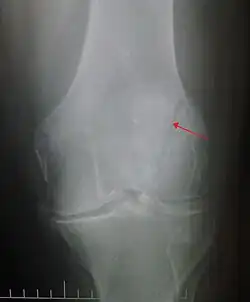

Transverse fracture of patella -